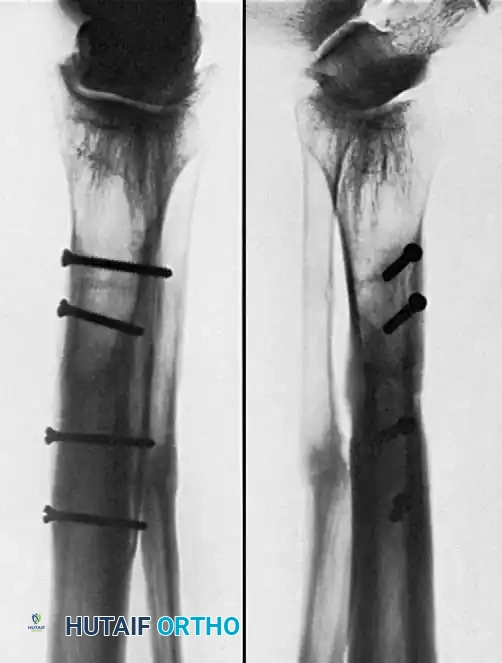

Associated Surgical & Radiographic Imaging